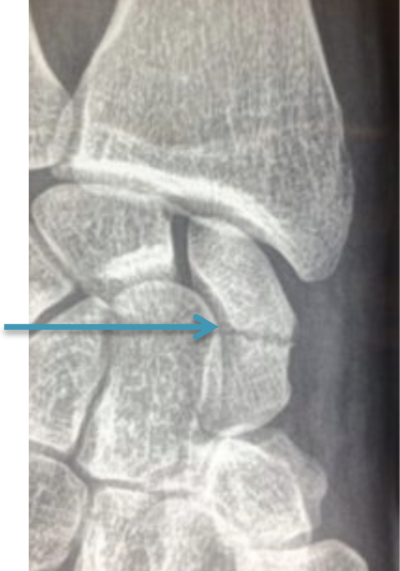

Elle passe fréquemment pour une entorse de poignet, et son diagnostic est parfois méconnu lors d’un premier examen par un médecin ou posé tardivement. Le diagnostic pourra être fortuit lors de la réalisation d’une radiographie suite à un autre traumatisme ou lors de la persistance de douleurs plusieurs mois ou années après un traumatisme.

Il faut réaliser une radiographie du poignet. En cas de doute, on peut réaliser un scanner qui permettra d’affirmer ou d’exclure le diagnostic de fracture du scaphoïde.